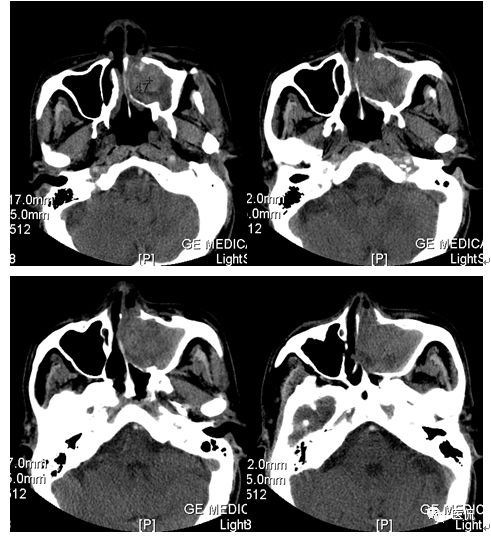

CT平扫及增强示:左侧上颌窦及鼻腔可见软组织密度影,呈膨胀性生长,周围骨质压迫性吸收破坏,累及左眶,病灶密度不均匀,周边区可见点状钙化,增动脉期轻度强化,局部见小灶性稍高密度区,静脉期病灶内见不均匀明显强化,CT值最高达117HU,延迟期强化范围有所增大。

本例病灶较大,周围骨质可见吸收破坏,并累及眼眶,病灶内少量钙化,增强扫描具有一定特征性,表现为动脉期轻度强化,局部见小灶性稍高密度区,静脉期病灶局部呈明显强化,CT值最高达117HU,延迟期强化范围有所增大,呈延迟渐进性强化的特点,推测为病灶内出血所致。